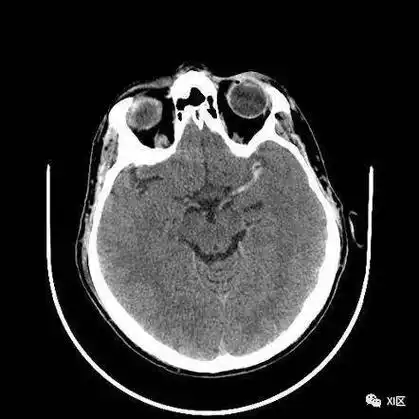

急性缺血性脑卒中多模式头颅ct图像解读